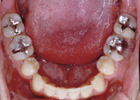

歯を抜いて治療した例 その1

治療前

治療途中

治療後